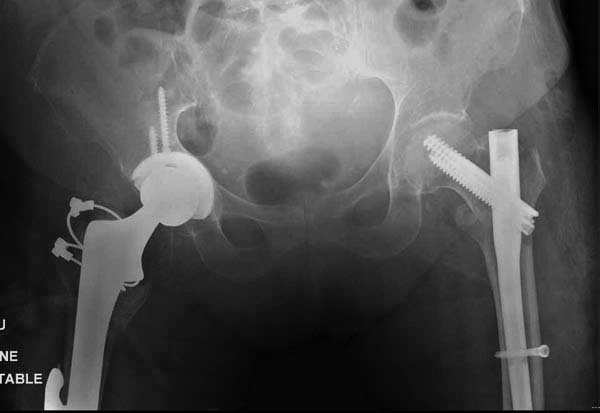

Третья операция-продолжения усилии "синьорами пэрами" по разрушению нормальной анатомии. Крест на головку! По видимому возраст позволяет биполярную конструкции, и при дефекте  calcar пошли на обычный цементный. Ягодичные мышцы потеряли связь с вертелом, т.е. отсутствует верхний удержатель, и результат “a Big Screw Up!” Снимки вызывают головокружение!

Такие “чужие осложнения” встречаются у всех и представляю банальный случай, который шаг за шагом показано как перерос в более сложный процесс... Больная 70 лет, множественные ко-морбидности, чрезвертельный перелом первоначально фиксирован Гамма 3. Осложнение в течение 6 недель, ревизия тотальной артропластикой и во время установки ножки обнаружена трещина диафиза (17), из малого доступа фиксация алло-графтом.

Имя     : 21 IT fx Rt replacement allo postop 3mnts.JPG

Тип     : image/jpg

Размер  : 37289 байтов

Описание: отсутствует

Url     : http://weborto.net:8080/pipermail/ortho/attachments/20120509/52aada75/attachment-0043.jpg